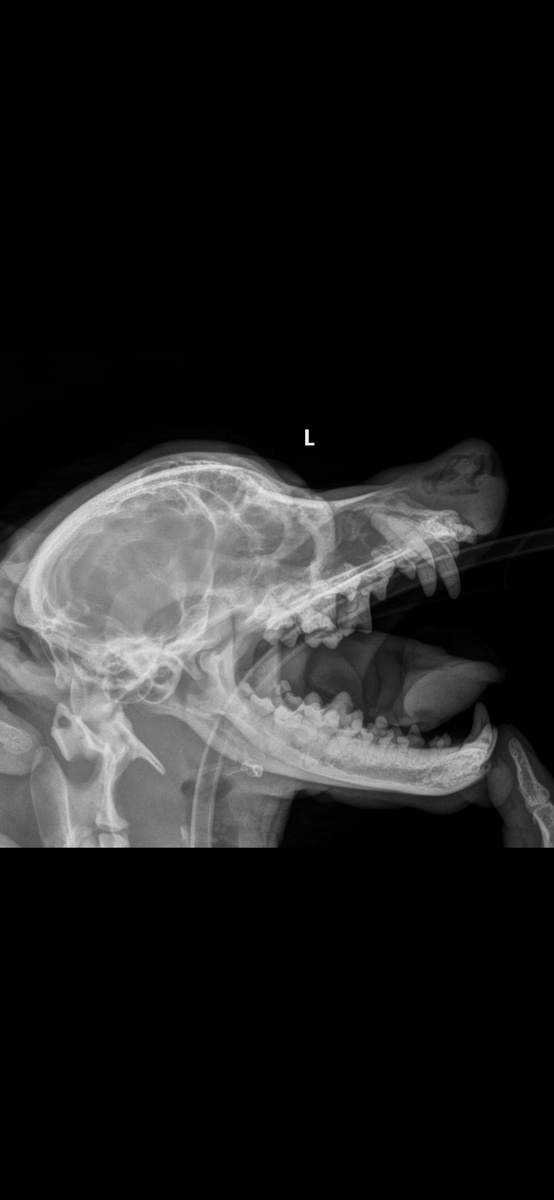

Рентген Тайсона

Сейчас у Тайсона возникли проблемы со здоровьем - затруднено дыхание. Нос не дышал, а из него начала появляться кровь.

Руслан поводу собаку в Донецк. После обследования у Тайсона были выявлены полипы, и ему была назначена операция.